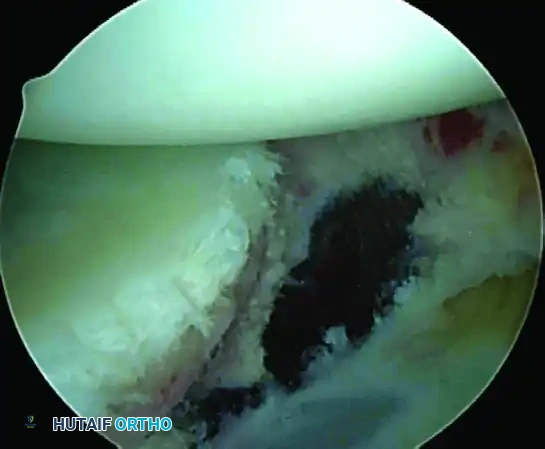

Identify the specific pathology. The spectrum of instability lesions includes soft tissue Bankart tears, bony Bankart lesions, Anterior Labroligamentous Periosteal Sleeve Avulsions (ALPSA), and Glenoid Labral Articular Disruptions (GLAD).

A, Soft tissue Bankart lesion.

B, Bony Bankart lesion.

C, Anterior labral periosteal sleeve avulsion (ALPSA).

D, Glenoid avulsion of glenohumeral ligament.

E, Glenoid labral articular disruption (GLAD).

F, Juvenile glenoid avulsion of the glenohumeral ligament.

1. Capsulolabral Mobilization and Glenoid Preparation

The most common cause of failure in Bankart repair is inadequate mobilization of the capsulolabral complex.

While visualizing from the anterosuperior portal, use an arthroscopic elevator or radiofrequency wand to meticulously free the capsule down to the 6-o’clock position. You must release the tissue until the underlying red muscle belly of the subscapularis is clearly visible. This complete release is mandatory to allow the inferior capsule to be shifted superiorly without tension.

💡 CLINICAL PEARL: The Biological Bed

Soft tissue healing requires a robust vascular response. Use an arthroscopic rasp or motorized burr to abrade the anterior glenoid neck down to bleeding cancellous bone. Do not over-resect the bone, as preserving the cortical edge is necessary for secure anchor purchase.

A, Abrasion of glenoid neck and capsular release to allow advancement of capsulolabral complex superiorly and laterally to restore anatomy and physiological tension.